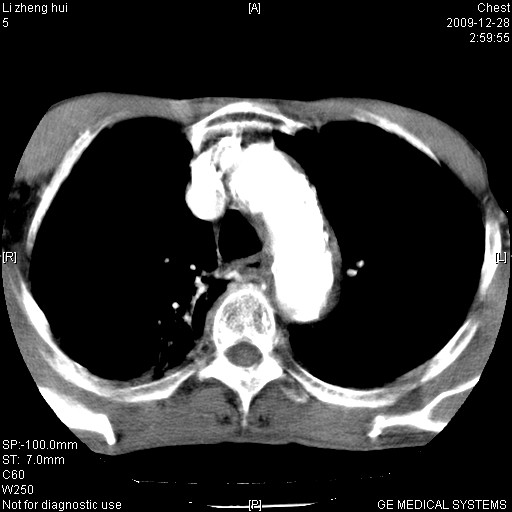

男  79岁 胸部痛急诊入院,晚上做的增强

考虑主动脉瘤?(增粗、钙化、壁血栓?)

支持降主动脉夹层

支持降主动脉瘤,不考虑夹层

动脉瘤伴附壁血栓

1)考虑胸主动脉壁间血肿或夹层动脉瘤。2)多发性肝囊肿。

1)考虑胸主动脉附壁血栓或夹层动脉瘤。2)多发性肝囊肿。